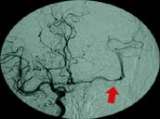

fig. 3: AFTER the procedure: an angiograph shows the reopening of the middle cerebral artery.

Richardson was given rTPA intravenously to help the body break down the blood clot. A small catheter from the femoral artery was simultaneously placed in the groin up through the blocked internal carotid artery and into and beyond the blood clot on the left middle cerebral artery were more rTPA was infused and was successful in reopening the majority of the middle cerebral artery (fig. 3).